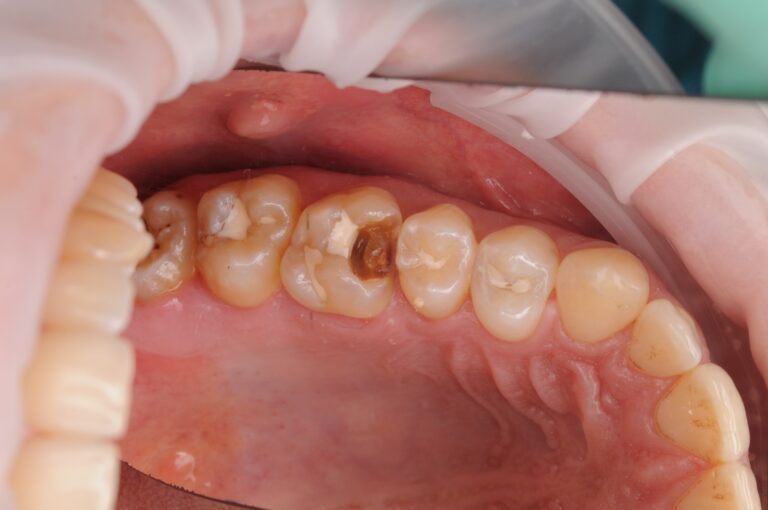

Second image: we remove the filling — and see the reality.

Under the filling — deep, extensive decay

that was not visible from the outside.

This is an important point:

If a filling doesn’t hurt, it doesn’t mean everything is fine.

Decay under a filling can develop quietly and slowly —

until it’s too late.